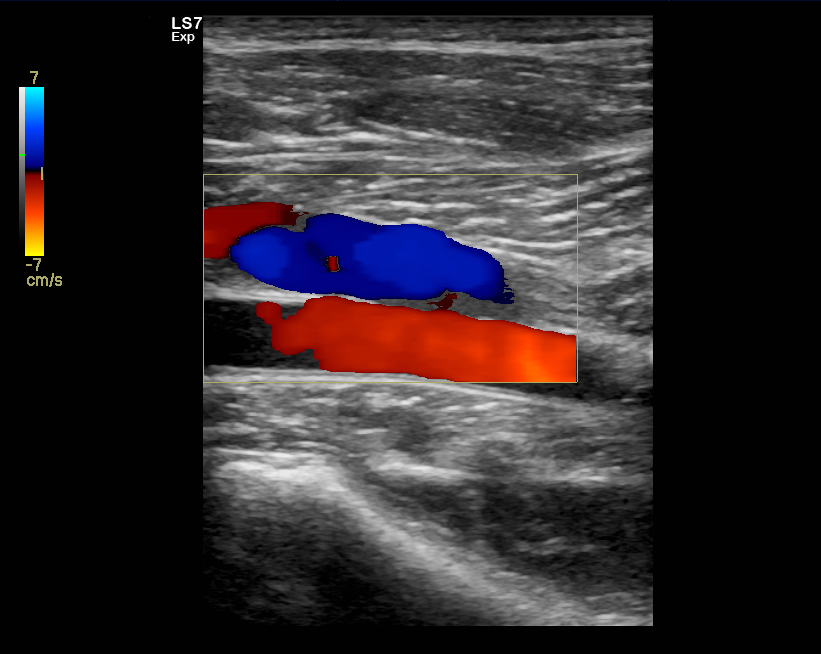

Laskimotukosten ultraäänitutkimus

Ultraääni on ensisijainen tapa selvittää mahdollisia laskimotukoksia. Alaraajojen turvotuksen syynä voi olla laskimotukos. Laskimotukosten ultraäänitutkimus on turvallinen, nopea ja helppo.